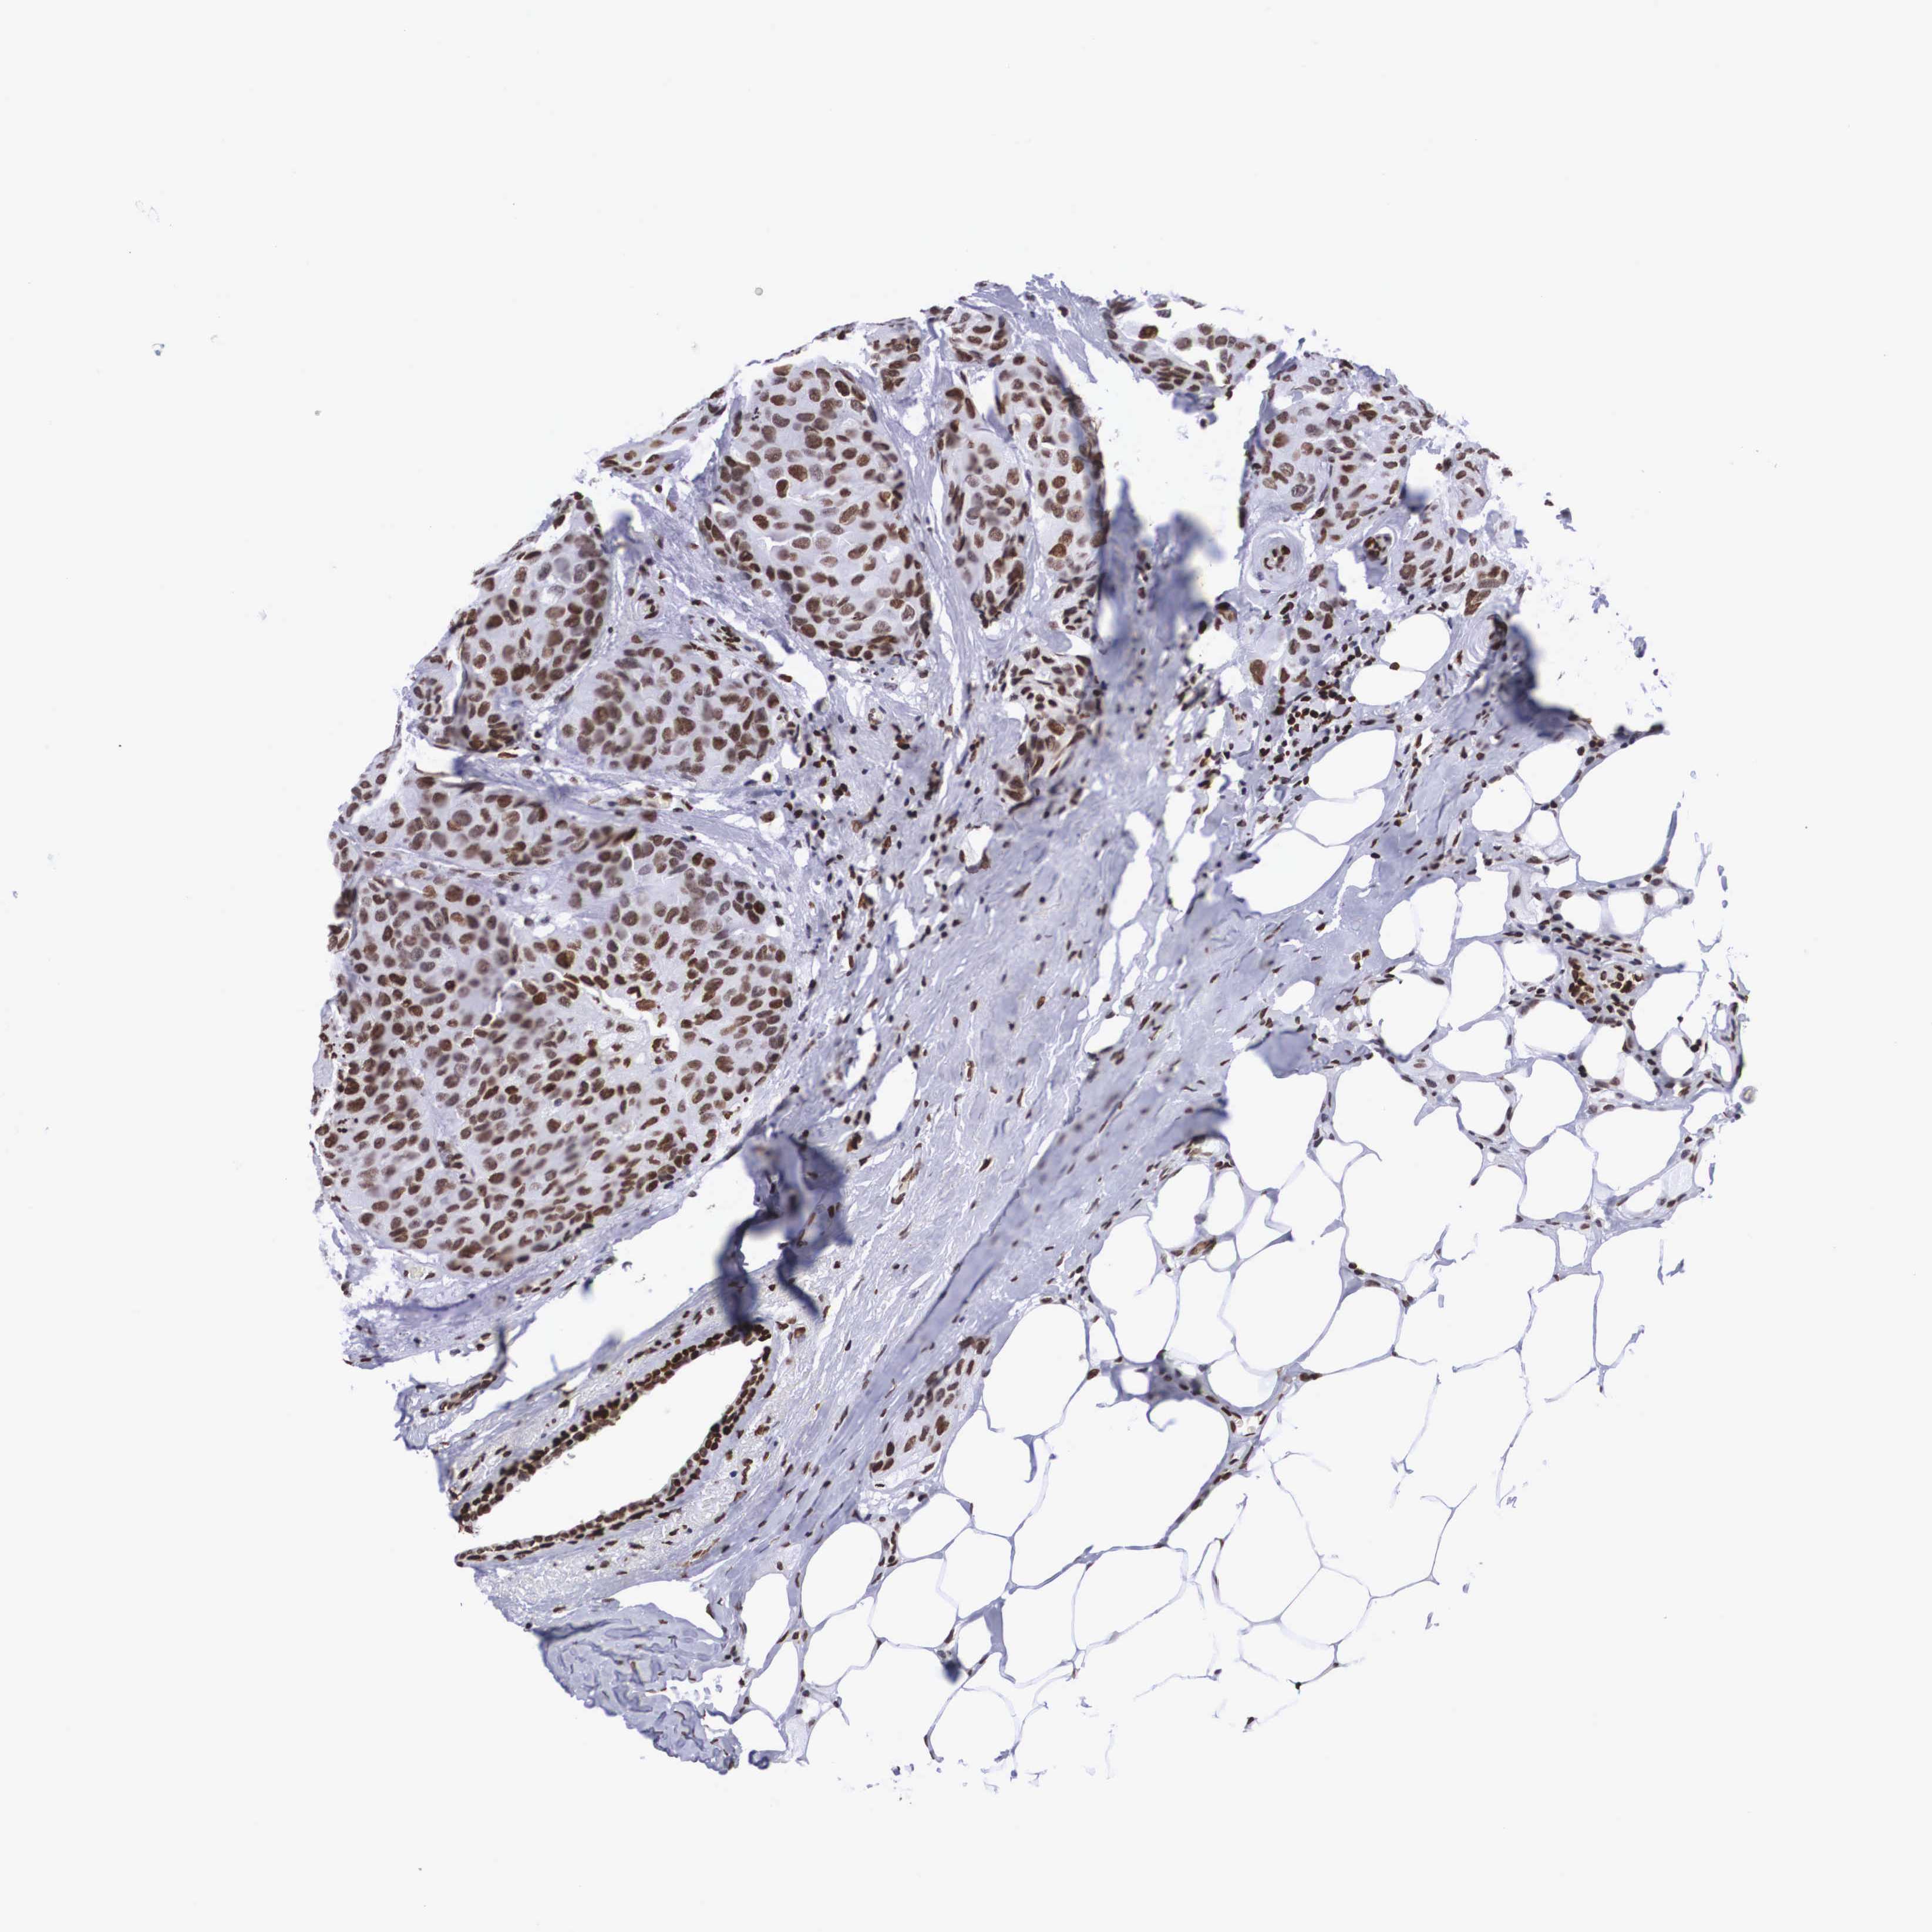

CANCER BREAST CANCER Show tissue menu

BRCA TCGA BRCA VALIDATION PROTEIN EXPRESSION